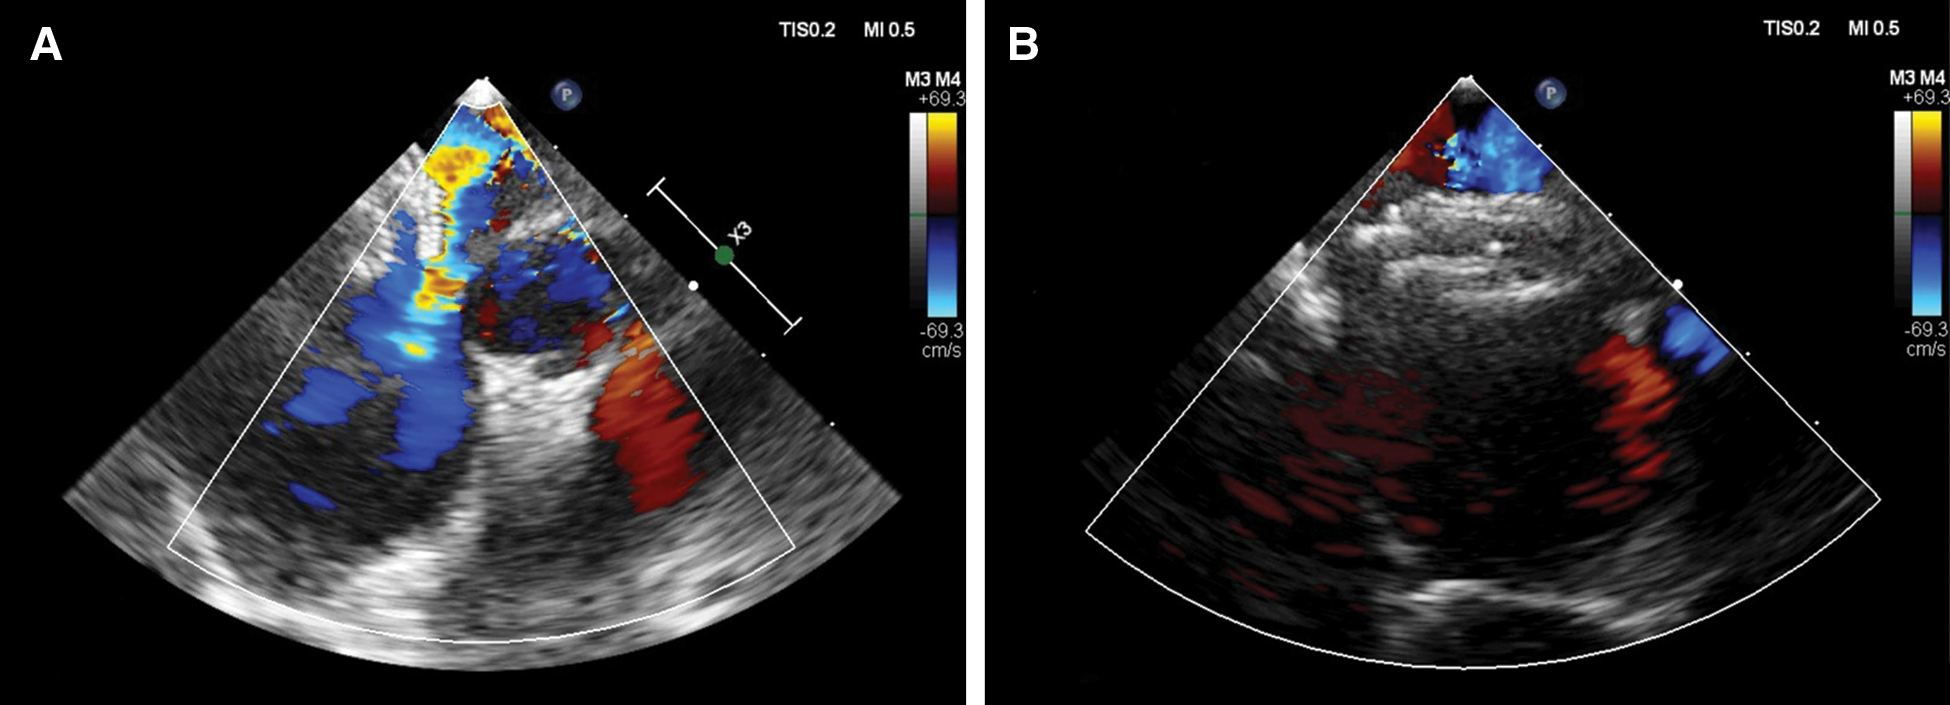

Transesophageal echocardiography (TEE) was performed under general anesthesia using the CX50 Philips ultrasound machine with X7-2t TEE probe for children with a body weight of >35 kg or the Affiniti 50 ultrasound machine with S7-3t TEE probe for children with a body weight of <35 kg (Philips Medical Systems, Andover, MA, USA). Multiple TEE views were used to assess the total interatrial septum length, ASD morphology, maximal ASD diameter, ASD rims, device position, and any residual shunt after device closure. Transcatheter device closure of ASD was performed under both echocardiographic and fluoroscopic guidance. A device 2–3 mm larger than the ASD diameter was selected [5]. However, if the aortic rim was deficient or the rims were floppy, a device 4 mm larger than the maximal diameter was selected. Two types of devices were used as regular septal occluders for oval defects and the Amplatzer cribriform septal occlude was used in case of a fenestrated septum and its size was determined by total septal length. In one patient, there were two defects, and the intervening tissue was 7 mm, so two devices were placed (one for each defect) “Figs. 3A and 3B”.

Figure 3: (A) TEE mid-esophageal short-axis view of a 3-year-old child with two ASDs where one was closed using a device and the other was shunting. (B) TEE four-chamber view showing two devices well-seated in place with no residual shunt